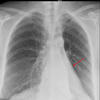

Comet tail sign

Rounded atelectasis

(Initially coined for tomography)